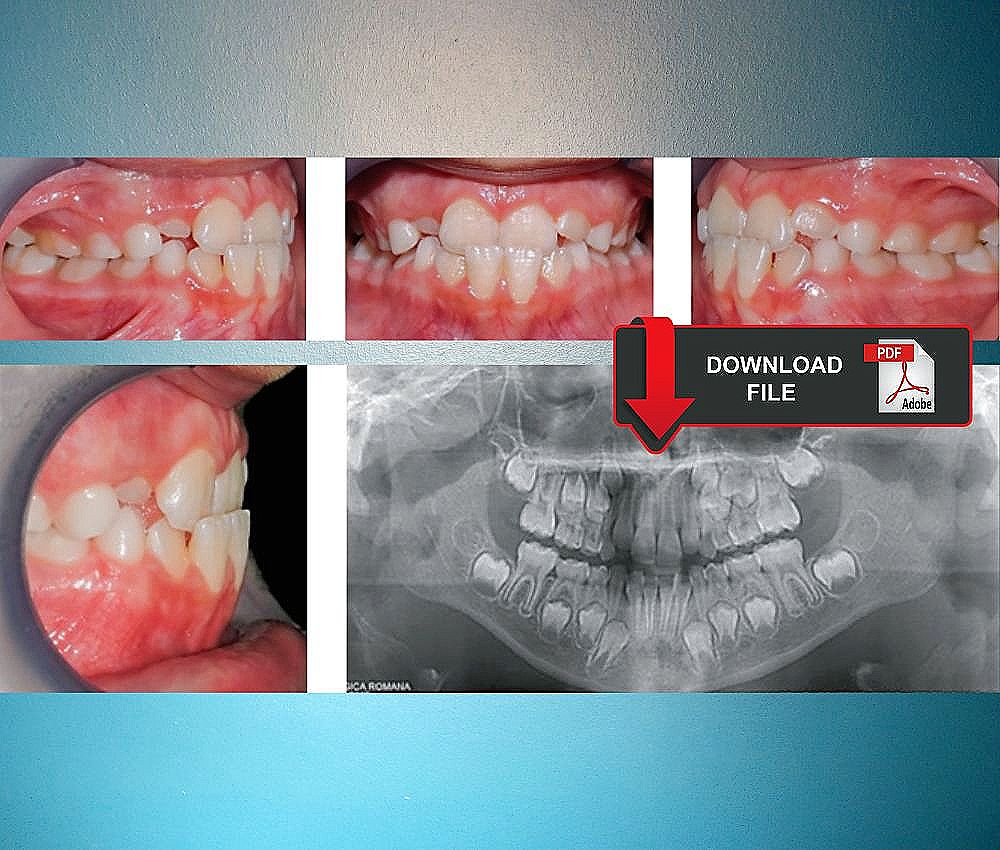

Intraoral Photographs Of The Patient In Mixed Dentition With Anterior

www.researchgate.net

www.researchgate.net

dentition bite intraoral premature transient bilateral primary

(PDF) Simple Removable Appliances To Correct Anterior And Posterior

www.researchgate.net

www.researchgate.net

crossbite dentition posterior intraoral extraoral correct

(PDF) Simple Removable Appliances To Correct Anterior And Posterior

www.researchgate.net

www.researchgate.net

crossbite dentition posterior correct radiograph extraoral intraoral